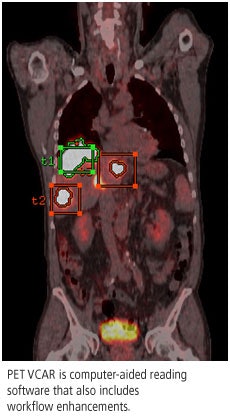

Finally, GE will highlight PET VCAR, a volume computer-aided reading application that received U.S. Food and Drug Administration 510(k) clearance earlier in 2007. The software includes workflow enhancements, such as exam-to-exam autoregistration, tumor segmentation and quantification, and multiplanar image review.